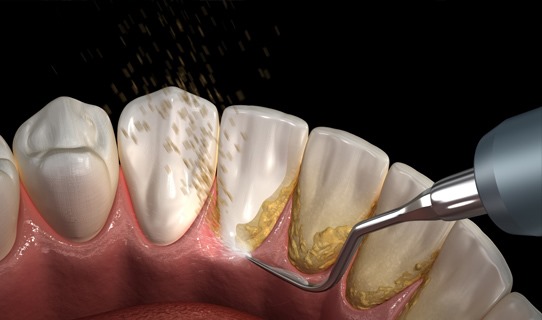

- - Limpieza y blanqueamiento.

Limpieza dental destartraje